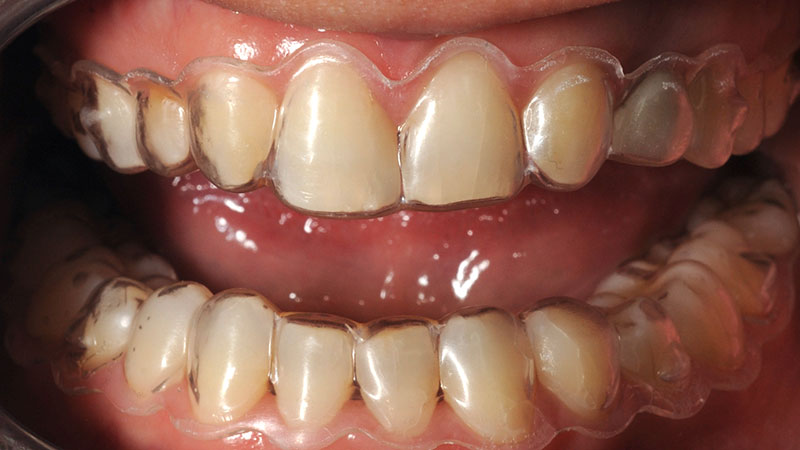

Лечение с алайнери за осигуряване на място за зъбни импланти.

– Провеждане на лечение с алайнери за осигуряване на място за зъбни импланти. И зъби с големина и форма като на дигиталния проект.